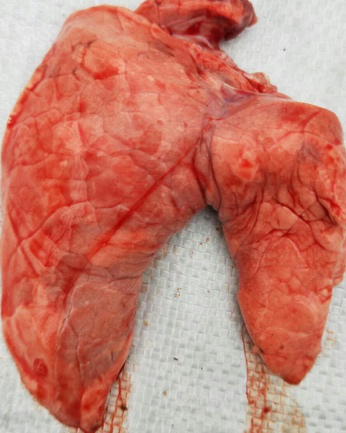

发病状态下的蓝耳总能看到典型的间质性肺炎,虽然间质性肺炎意味着病毒性疾病,但是更多的可能是蓝耳,很多疾病和血管有密切关系,蓝耳病毒具有嗜肺性特点,肺作为机体最大的毛细血管网,可以很好的衡量疾病的感染压力和发病程度,这种形态的肺,预示着猪场有严重的病毒感染压力。大体解剖中,间质性肺炎的特点是肺立体感增强,不塌陷,由于肺泡壁增生而会导致整个肺体积在胸腔内异常增大,因此典型的间质性肺炎有时候会看到特征性的肋骨压痕。

图片来源于蓝耳不稳定场

蓝耳感染早期肺形态图片,左面图基本可以认为是正常肺,可以很好的萎缩塌陷,右面的肺发病中晚期,这两种肺都是可以检出蓝耳病毒的,病毒感染早期有时候无法还无法形成肉眼可以鉴别诊断的临床症状,中期和晚期发病的猪的大体病变是有很重要的诊断意义,中图显微病变为轻度的间质性肺炎,显微病变可以很好的衡量发病与否

图片来源于蓝耳很不稳定场